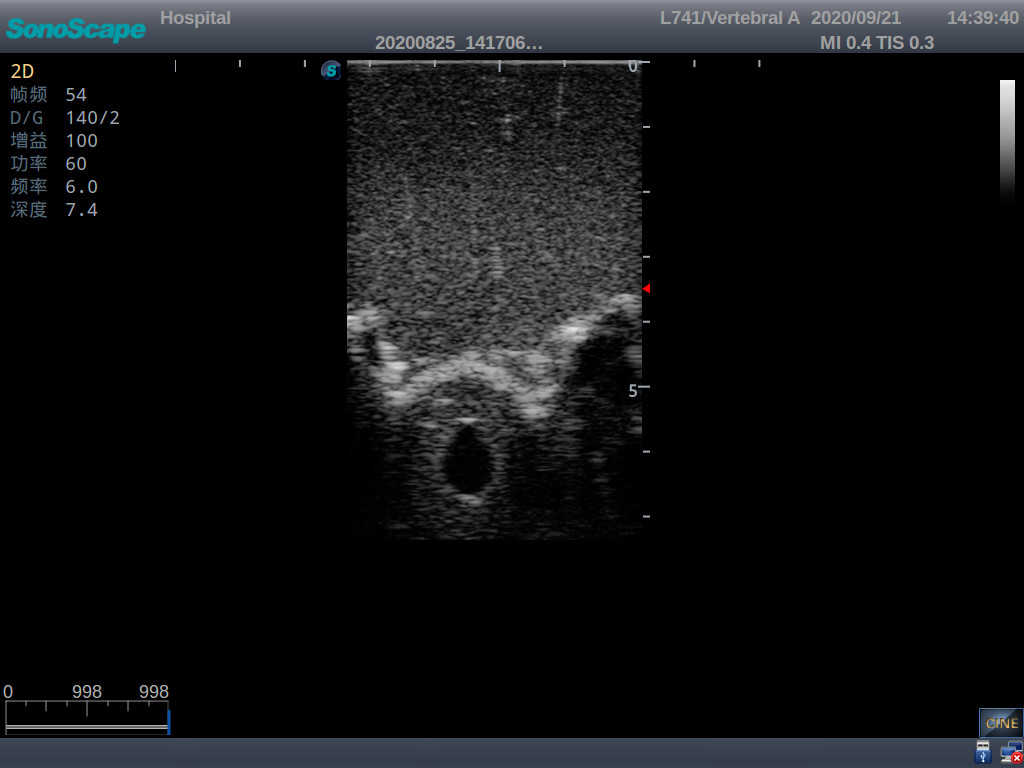

Model TYE1549.2

This model is an ideal choice for ultrasound-guided adult lumbar puncture training with true-to-life skin feel and touch, accurate anatomical structures as well as real clinical ultrasound images. Realistic resistance to needle tips and correct landmarks provide excellent hands-on experience.

Accurate anatomical structure of L1-L5 and the vertebral canal

2)  Real clinical ultrasound images